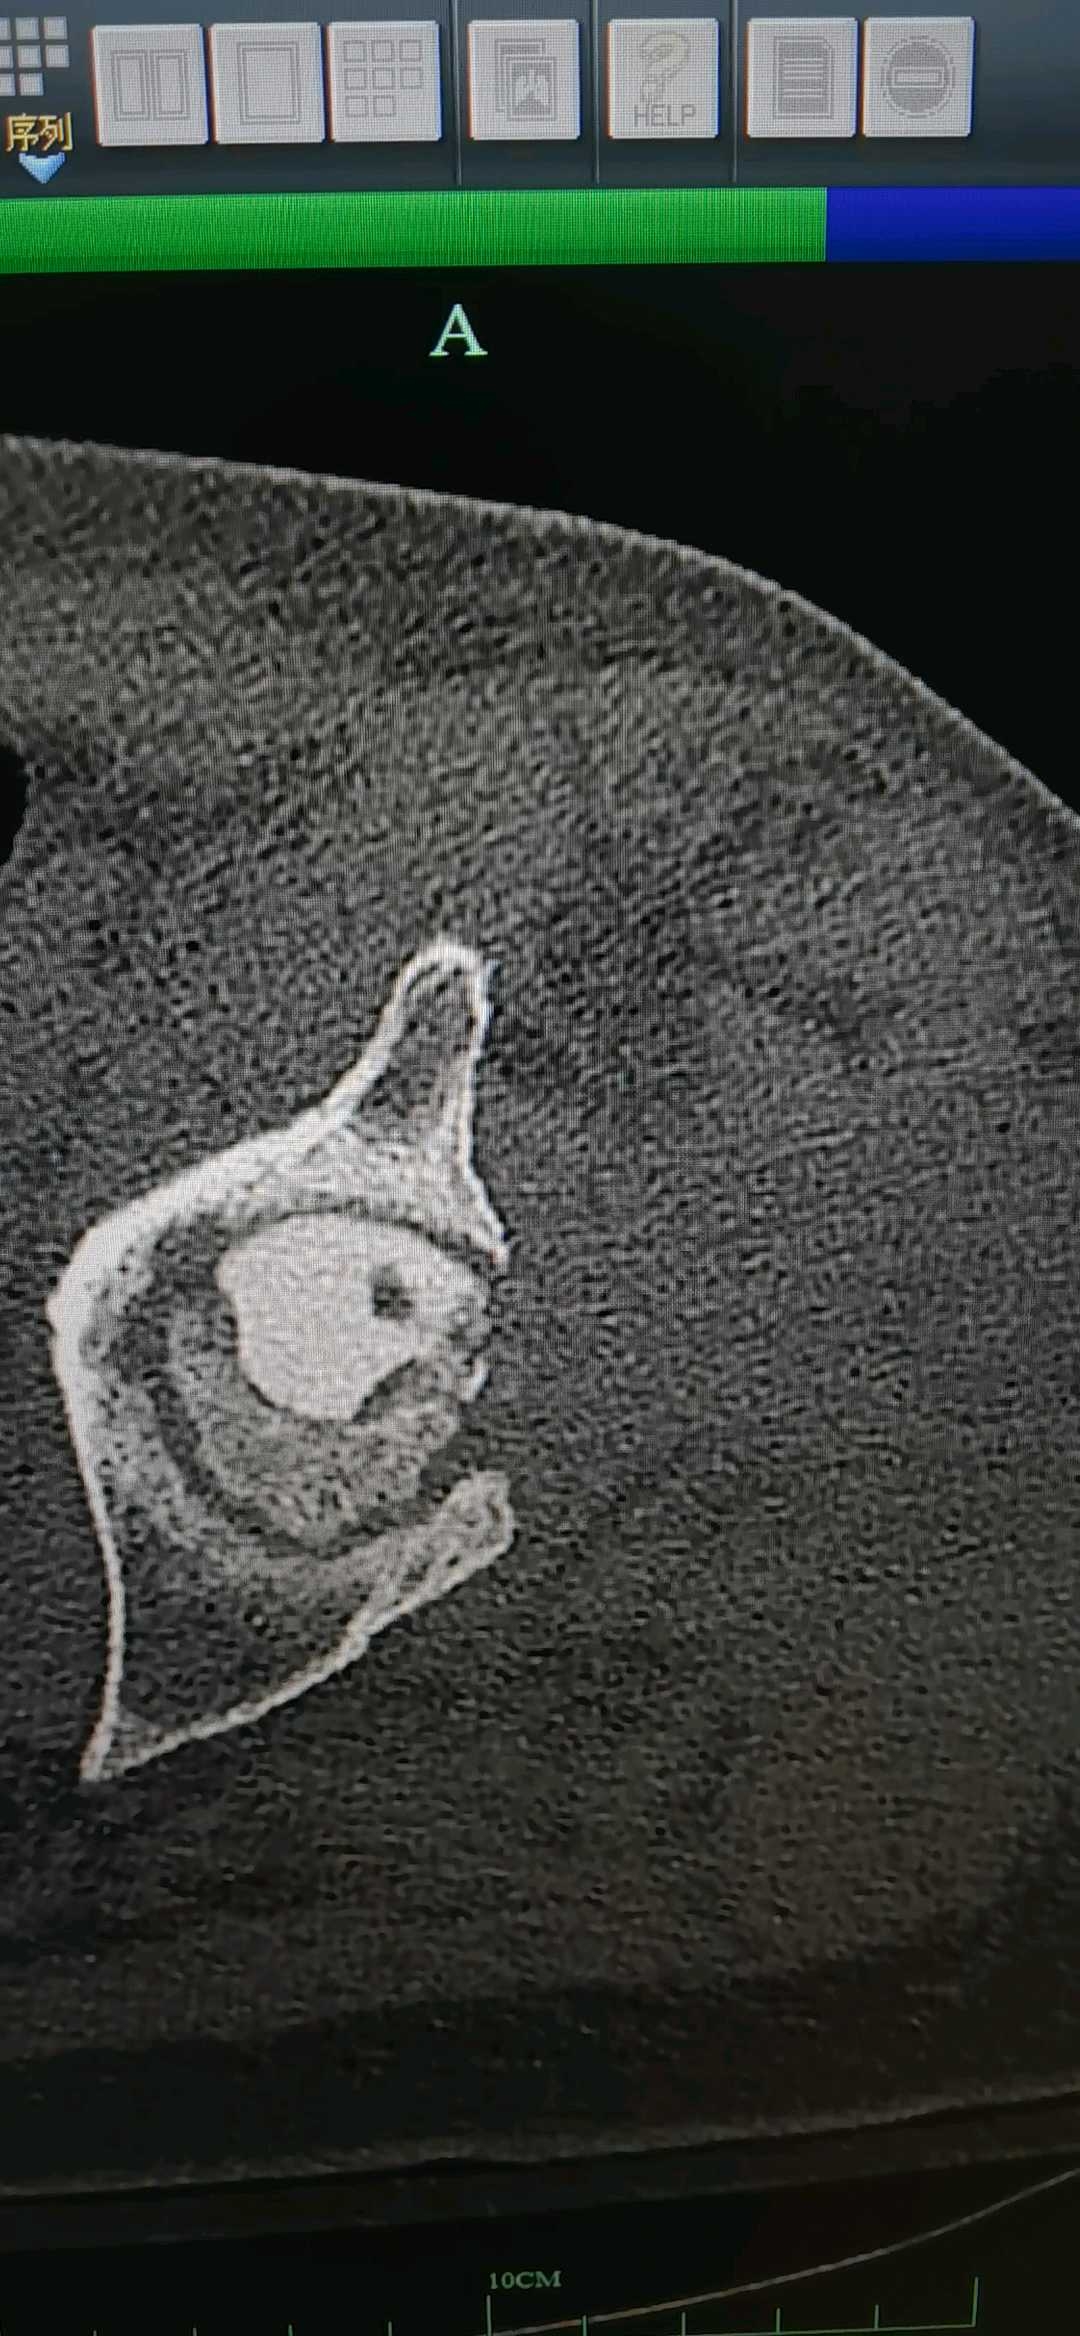

局部磁共振,ct阴性

这次用血管钳抵了一把,本来朝下的导针,朝向股骨头圆心。避开之前术后残留的坏死区域(也不知道里面塞了啥东西,既往病史不详)。